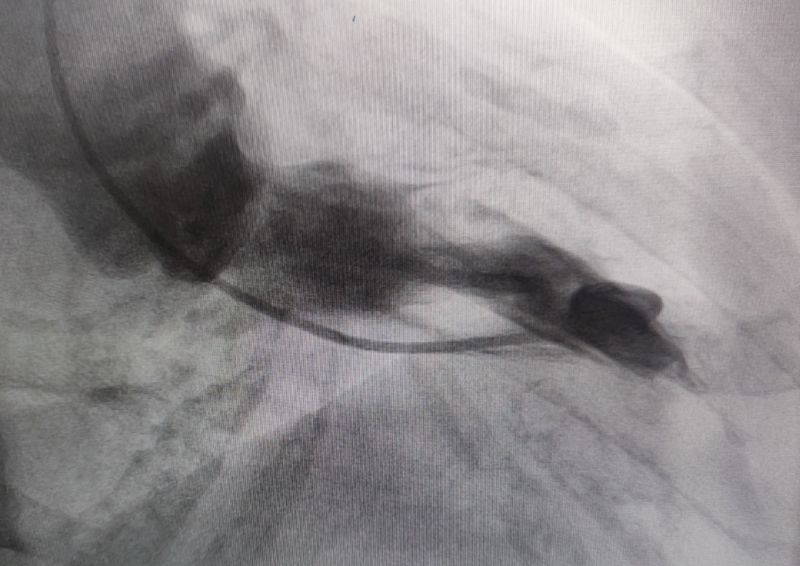

術(shù)前

面對這一復(fù)雜病情,崔旭輝主任醫(yī)師、馮韓章副主任醫(yī)師團(tuán)隊展開了全面且深入的評估討論。經(jīng)審慎分析,最終確定室間隔化學(xué)消融術(shù)(PTSMA)為最佳治療方案。PTSMA是通過導(dǎo)管將無水乙醇精準(zhǔn)注入供應(yīng)肥厚室間隔的間隔支血管,利用化學(xué)作用使血管閉塞,促使肥厚的室間隔缺血、壞死、變薄,有效降低或消除室間隔心肌收縮力,從而拓寬心室流出道、緩解梗阻癥狀,顯著改善患者的臨床狀況。